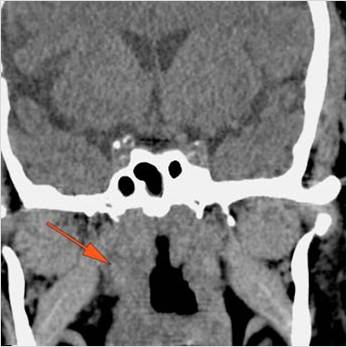

There is infiltration of the fat surrounding the nasolacrimal sac.

There is soft tissue infiltration or bone erosion along the nasolacrimal fossa or canal.